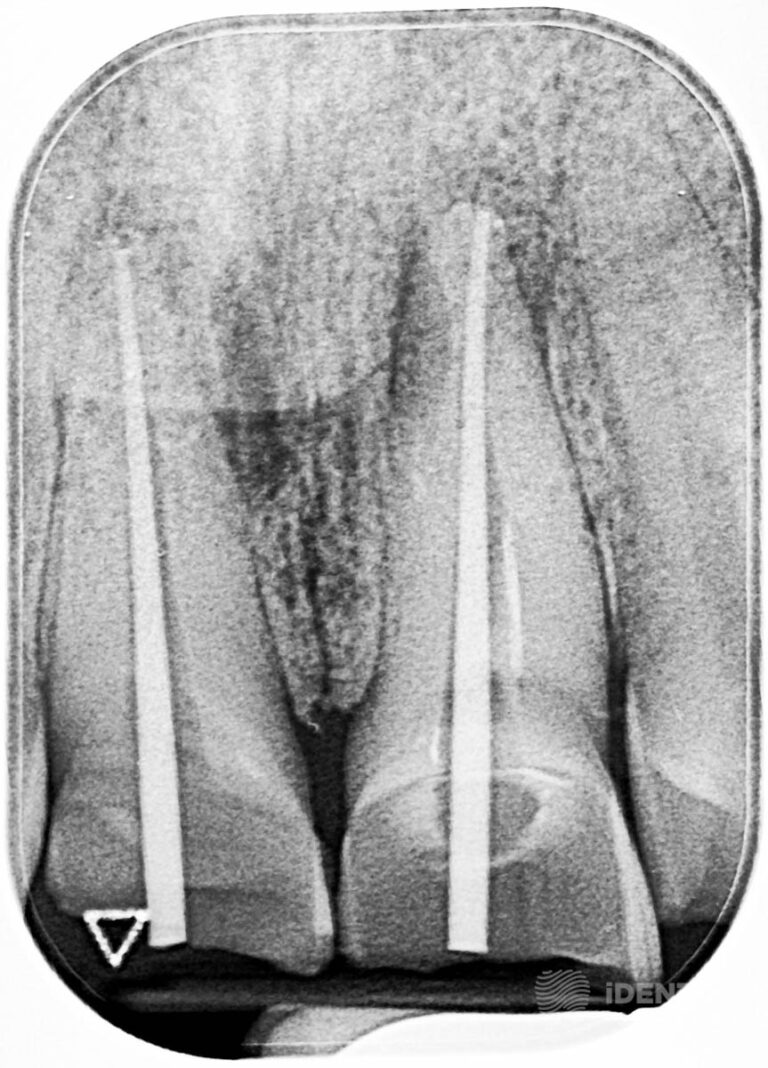

A gyökérkezelés megkezdése előtt preoperatív CBCT felvételt készítettünk a páciensről, melyen meghatároztuk a gyökércsatornák becsült munkahosszait.

A fogak trepanációja (gyökércsatornák megnyitása, ill. feltárása), majd a fogbél exstirpációja (ér, ill idegképletek eltávolítása) után feltágítottuk (csatornák faláról a fertőzött fogagyag eltávolítása) a csatornákat az előzetesen meghatározott munkahosszon. Ezt követően ellenőrző röntgenfelvételt készítettünk (guttapercha-kontroll).